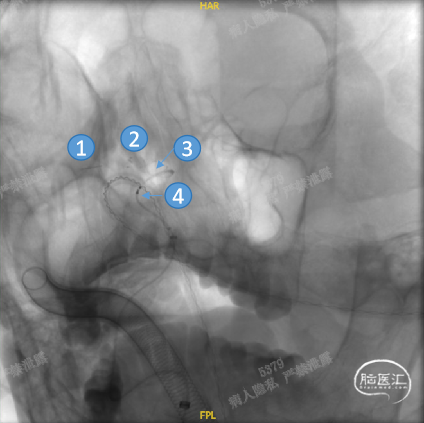

正位

①输送导丝头端

②支架远端扩口显影点

③工作区螺旋显影丝

④支架近端扩口显影点

平衡释放支架中段,过弯时确保系统头端处于血管中央,观察到支架自膨打开后,轻推支架以保证支架贴壁。确定近端着陆点处于血管平直区且贴壁良好后,平衡释放支架末端并解脱。

工作角度